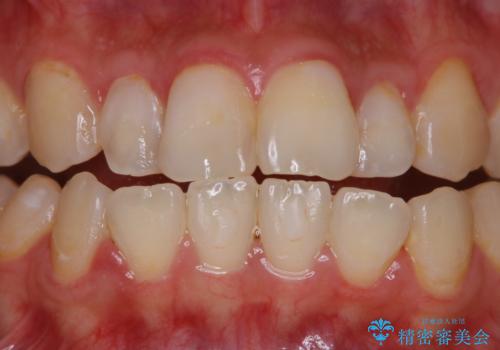

歯面がバイオフィルム(細菌の塊)や歯石で覆われていました。

PMTC(自費クリーニング)で、専門的な器具を使用し、歯石を砕き、バイオフィルムを剥がし、トリートメントまで行いました。歯肉が腫れていたため、バイオフィルムや歯石を取り除いたことにより、施術後の歯肉から出血が見られます。ただし、出血は次第におさまります。

PMTC(自費クリーニング)はホワイトニングではないため、歯が白くなることはありませんが、徹底的に汚れを除去しますので、ご自身本来の歯面となり、艶がでて明るい印象となります。